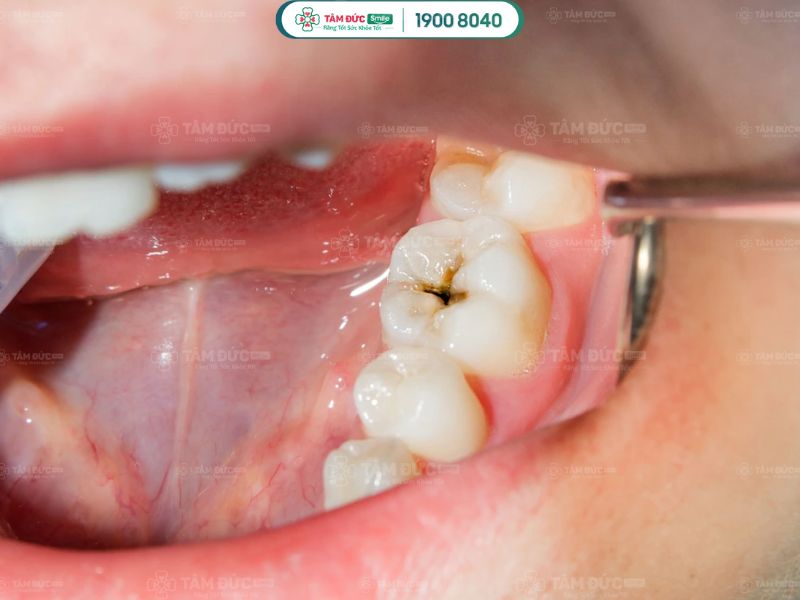

2.1. Mắc bệnh sâu răng

Không đánh răng mỗi ngày tạo điều kiện cho vi khuẩn phá hỏng men răng, hình thành chấm nhỏ li ti. Lâu dần, vi khuẩn gây ra các lỗ hổng lớn trên bề mặt răng. Những lỗ hổng này ngày càng phát triển rộng hơn, phá huỷ răng và làm Quý khách bị đau nhức, ê buốt.

Không đánh răng trước khi ngủ dễ bị sâu răng